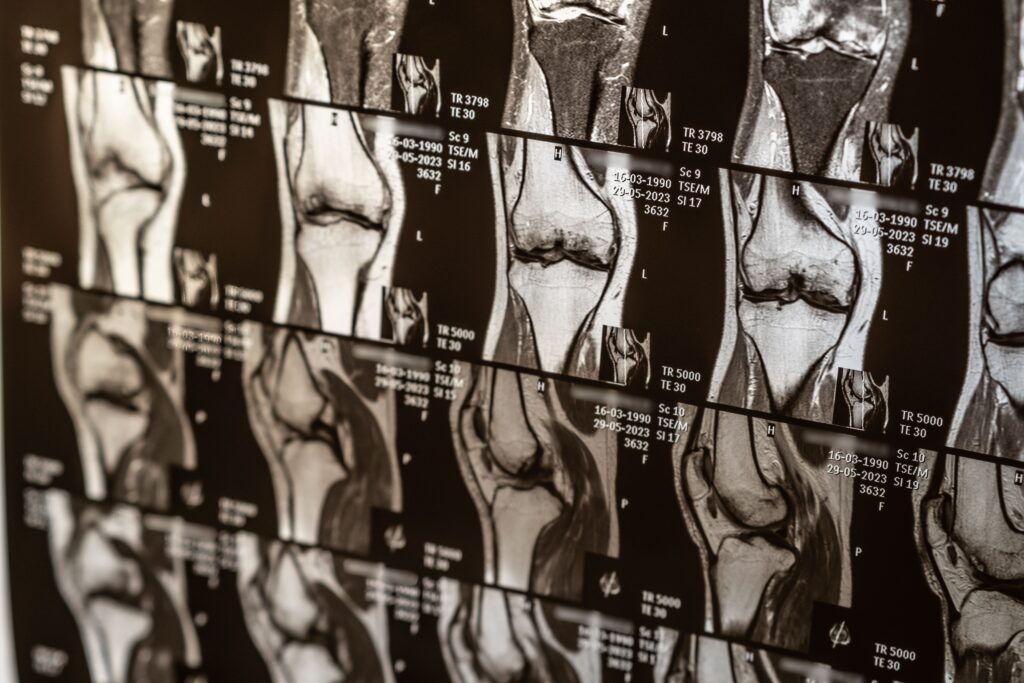

Pruebas de imagen

- Radiografías: muestran el espacio articular (indirectamente la cantidad de cartílago).

- Resonancia magnética (RMN): la prueba más útil para visualizar directamente el cartílago, determinar el grado de desgaste y detectar lesiones asociadas.